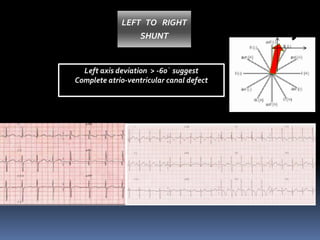

Left axis deviation > -60᷁ suggest

Complete atrio-ventricular canal defect